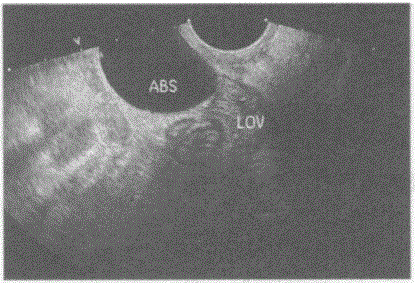

问题 临床资料:女,41岁,子宫全切术后。妇科内诊:盆腔可触及肿物,质软。 超声综合描述:经阴道扫查左附件区可见腊肠样无回声区,内透声清亮。 超声提示:

选项 A.左输卵管积水 B.左卵巢囊肿 C.左卵巢冠囊肿 D.盆腔包裹性积液

答案 A